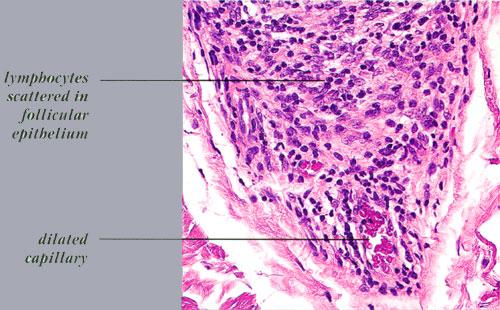

Lymphocytes may also be seen sparsely infiltrating the matrix epithelium of anagen follicles, inducing damage to the matrical cells that includes intra- and intercellular edema, cellular necrosis, and microvesicle formation. One of the earliest findings was shown to be a loss of structural integrity of bulbar keratinocytes in the central part of the supramatrical bulb and shrinkage of hair bulbs toward a club shape . As a result of injury to bulbar melanocytes and keratinocytes, pigment casts, which are clumps of melanin pigment, may be found within the dermal papilla, the sheath of miniaturizing or regressing follicles, or the follicular epithelium . Pigment casts

are more often found in trichotillomania; one interpretation of their presence in the context of AA is that here too they represent external manipulation of the hair . Pigment casts have also been found in postoperative pressure-induced alopecia, leading those authors to postulate that they resulted from the sudden conversion of follicles from anagen to catagen, as occurs in trichotillomania and AA .